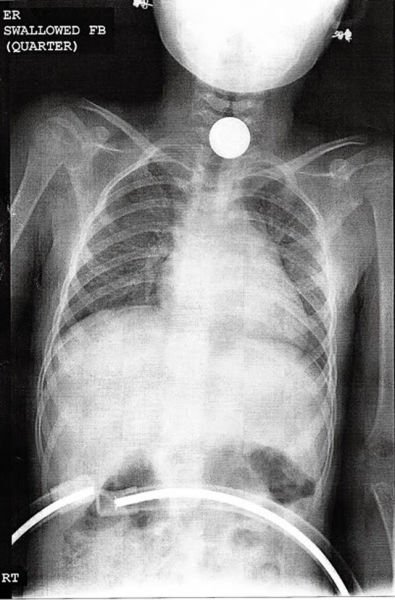

На этом снимке виден четвертак, проглоченный шестилетней девочкой.![]()